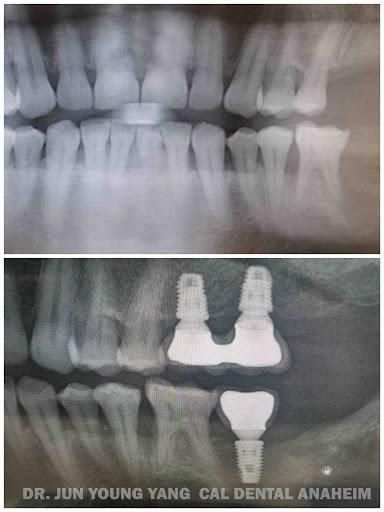

Cal Dental Group

I wonder why I waited so many years to get my implant and my teeth whitened., I was always embarrassed of my tooth color. Dr gave me the smile I always deserved. His staff was professional and made me feel very comfortable about the process. I am so grateful at Dr Youn and his attention to detail. I highly recommend Dr..Youll be so glad you made the decision. Yoli